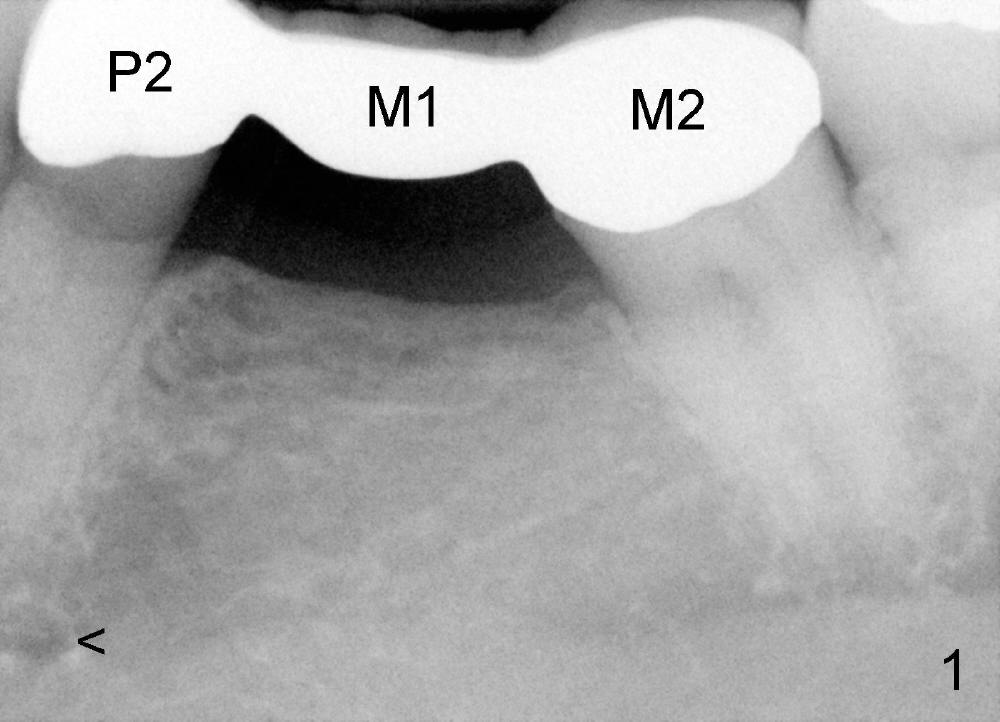

五年前童太太随童医生退休从外州到亚特兰大(Atlanta)定居,他们两人均成为我们病人,初诊常规拍摄几张X光片(包括图一:左下牙桥:P2第二前磨牙,M1第一磨牙,M2第二磨牙)。四年前六十九岁童太太右下第一磨牙根尖炎复发,应该拔除做植牙,但是她害怕手术,所以我们重做根管治疗,但是还是失败,最终拔牙,植牙,一切很顺利。后来小巧玲珑童太太透露她一直服用骨质疏松药物(Fosamax),而且近三年静脉注射骨质疏松药物(Reclast)。但愿她永远没有牙齿问题,不再需要拔牙植牙。

在第二前磨牙植牙困难在于:第一第二前磨牙牙根很接近(图二),另外,颏孔(mental foramen and nerve)也很接近第二前磨牙根尖(图二黑箭头,与图一比较),其实在这种条件下立即植牙反而容易,牙根长度帮助我们确定植牙长度,牙槽窝愈合后我们就没有这个优势了。如果术中牙槽窝出血不多,骨壁不健康,我们可能会悬崖勒马。拔牙植牙后骨坏死也可以处理。

病人服用Amoxicillin后症状好转很多,第二次回诊所再次诊治,我们怎么治疗呢?有人怀疑以上诊断吗?请比较图一,图二(白箭头)。